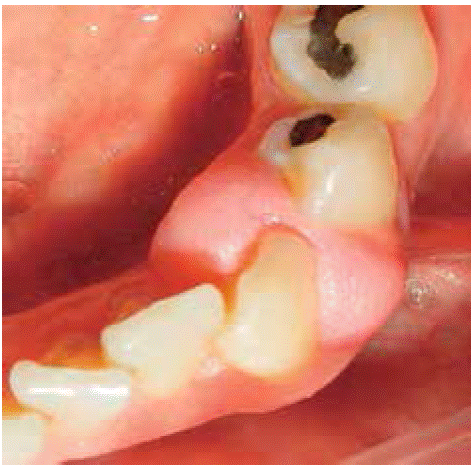

Clinical examination revealed inflammatory gingival lesion approximately measuring 9x9 mm, partially covering the clinical crown's lingual and vestibular areas. The lesion was firm, smooth and lobulated (Figures 26and27). Periodontal evaluation revealed presence of plaque and calculi, as well as a 40% (O'Leary) oral hygiene index.

Treatment: oral hygiene instruction and excisional biopsy with gingivoplasty.